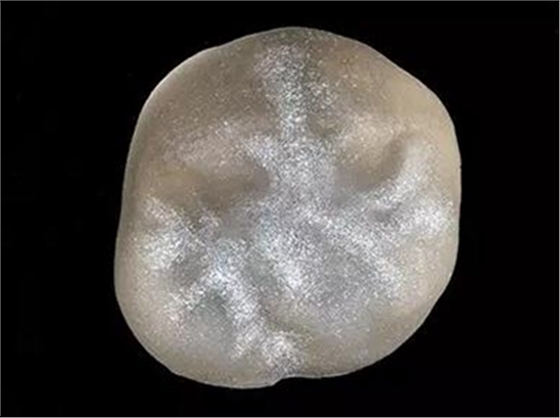

結(jié)晶前

在結(jié)晶燒結(jié)之前設(shè)計(jì)完成切削的修復(fù)冠。